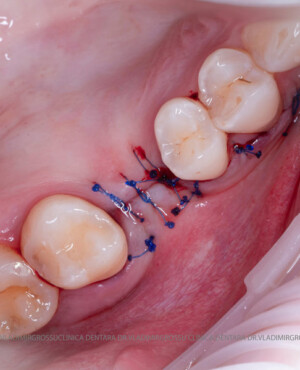

Un element esențial în procedura de aditie osoasă este utilizarea membranelor biologice, care izolează materialul osos de țesuturile moi (gingie) pe durata procesului de vindecare. Cele mai recomandate sunt membranele resorbabile din colagen sau pericard.

Adiția de gingie (gingivoplastia)

Aditia gingivală este o procedură chirurgicală ce corectează diverse probleme estetice și funcționale, cum ar fi recesiunea gingivală. În implantologia modernă, aditia de țesut moale este utilizată aproape în fiecare intervenție de inserție a implantului dentar pentru a asigura un aspect estetic natural și o bună integrare a implantului în cavitatea bucală.